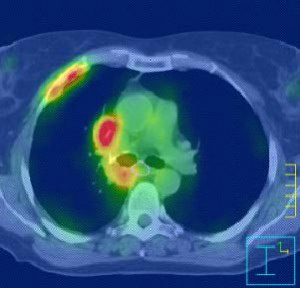

Η ακτινοχειρουργική με CyberKnife αντιπροσωπεύει μία πανίσχυρη και μεγάλης ακρίβειας τεχνική για ασθενείς με αρχική, υποτροπή ή μεταστατική εντόπιση όγκου στον πνεύμονα. Η θεραπεία είναι ασφαλής να δοθεί σε ασθενείς που δεν μπορούν λόγω άλλων παθολογικών καταστάσεων να χειρουργηθούν και  προσφέρει μία πολύ καλή θεραπευτική επιλογή σε ασθενείς με υποτροπιάζουσα ή εμμένουσα νόσο που πριν είχαν ελάχιστες αν όχι καμία, δραστική θεραπεία ικανή να τους βοηθήσει.